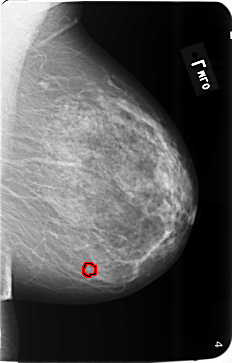

B_3493_1.RIGHT_MLO

RIGHT_MLO LINES 5808 PIXELS_PER_LINE 3728 BITS_PER_PIXEL 12 RESOLUTION 50 NON_OVERLAY

FILE: B_3493_1.LEFT_MLO.OVERLAY

TOTAL_ABNORMALITIES 1

ABNORMALITY 1

LESION_TYPE CALCIFICATION TYPE PLEOMORPHIC DISTRIBUTION CLUSTERED

ASSESSMENT 4

SUBTLETY 3

PATHOLOGY BENIGN

TOTAL_OUTLINES 1

BOUNDARY